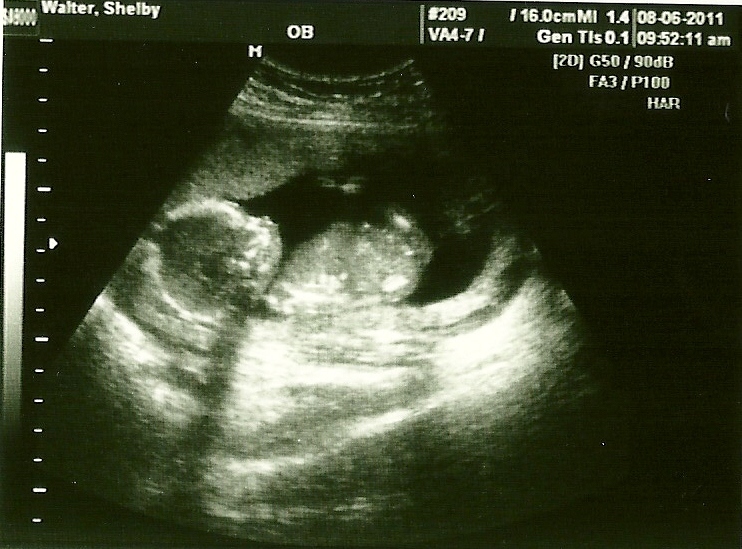

OK, super exciting news first... we found out yesterday (for positive) that we are having a BOY!!!

ultrasound done and find out for sure. The tech said he has never been wrong in over 30 years and said we are for sure having a BOY!! What was even more special was Hannah was able to be there, hear the heartbeat, and see her little brother moving around on the screen. We were both nervous she wouldn't be excited since it wasn't a sister, but she was absolutely thrilled and hasn't called the baby Emily since we've found out! If it's possible, she seems even MORE excited and loving now towards my baby bump since she knows what's growing inside! I love seeing the growing love she has for her baby brother and I can't wait to see how she acts when he's actually here!

Hands in front of his face.

Beautiful, perfect spine.

Cute little boy profile and growing tummy!